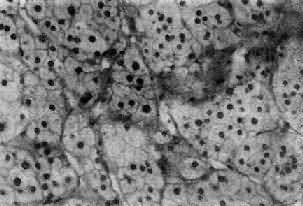

肾上腺皮质腺与局灶性结节性增生的病变相似,两者可以并发。腺通常是单侧单发性,并有薄层包膜,对周围组织有压迫现象,为鉴别的主要点。大小直径为1~5cm,切面黄色,有时呈红褐色,镜下多为类似束状带的泡沫状透明细胞,含有丰富类脂质,有时由类脂含量少的嗜酸性细胞构成,或者两种细胞混合存在。细胞排列成团,由含有毛细血管的少量间质分隔(图15-16)。部分腺为功能性,可引起醛固酮增多症或Cushing综合征,在形态上与非功能性腺没有区别。

图15-16 肾上腺皮质腺